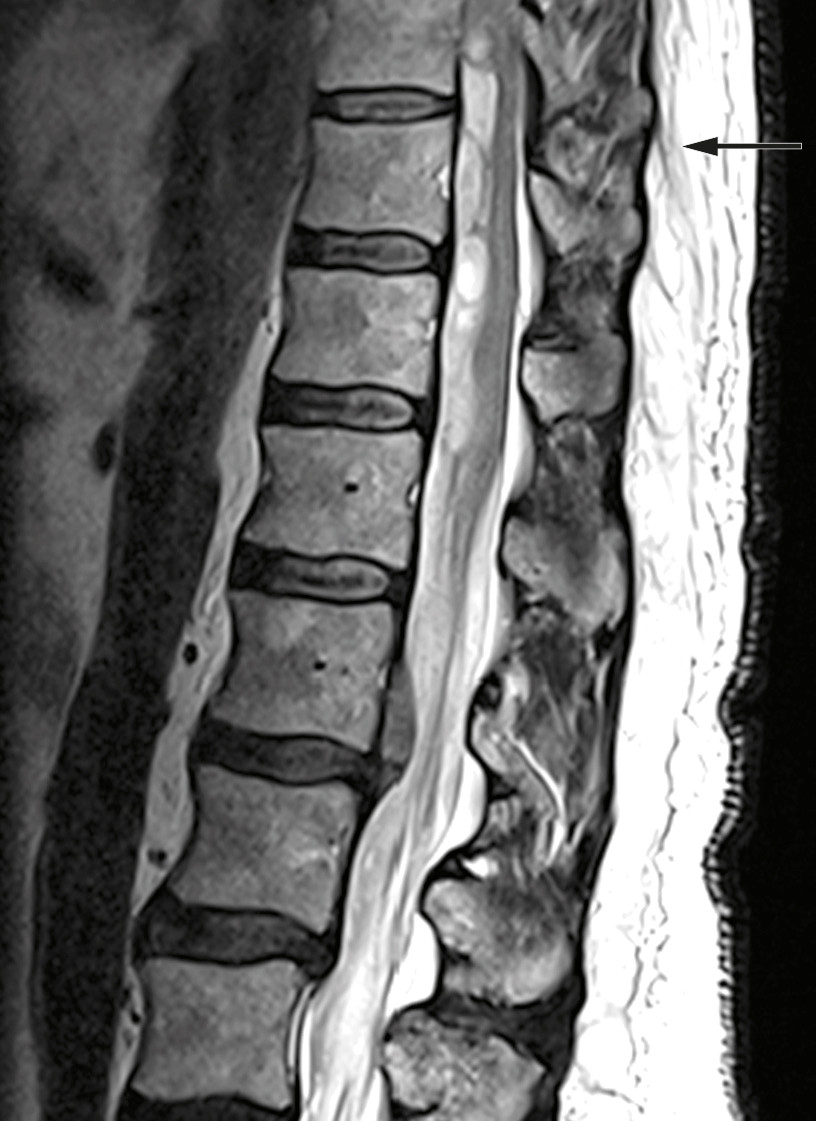

Examination upon admission showed blood pressure 146/68 mm Hg, heart rate 70 beats/min, Hb 15.4 g/dl (reference range 13.4–17.0 g/dl), platelets 241 ∙ 109/l (145–390 ∙ 109/l), creatinine 72 µmol/l (60–105 µmol/l) and Quick INR 2.6 (within the therapeutic range of 2–3). MRI revealed an intraspinal subdural haematoma at levels Th9–L1 with dislocation of the spinal cord and medullary cone (Figure 1). CT angiography showed no evidence of vascular malformation or arteriovenous fistula. Based on interpretation of an acute MRI, the patient was given phytomenadione (Konakion, 10 mg) and prothrombin complex concentrate (Octaplex, 2 500 IU), dosed according to the recommendations of the Neurology-Norwegian Electronic Medical Handbook ('NevroNEL') (4), to avoid further haemorrhaging.